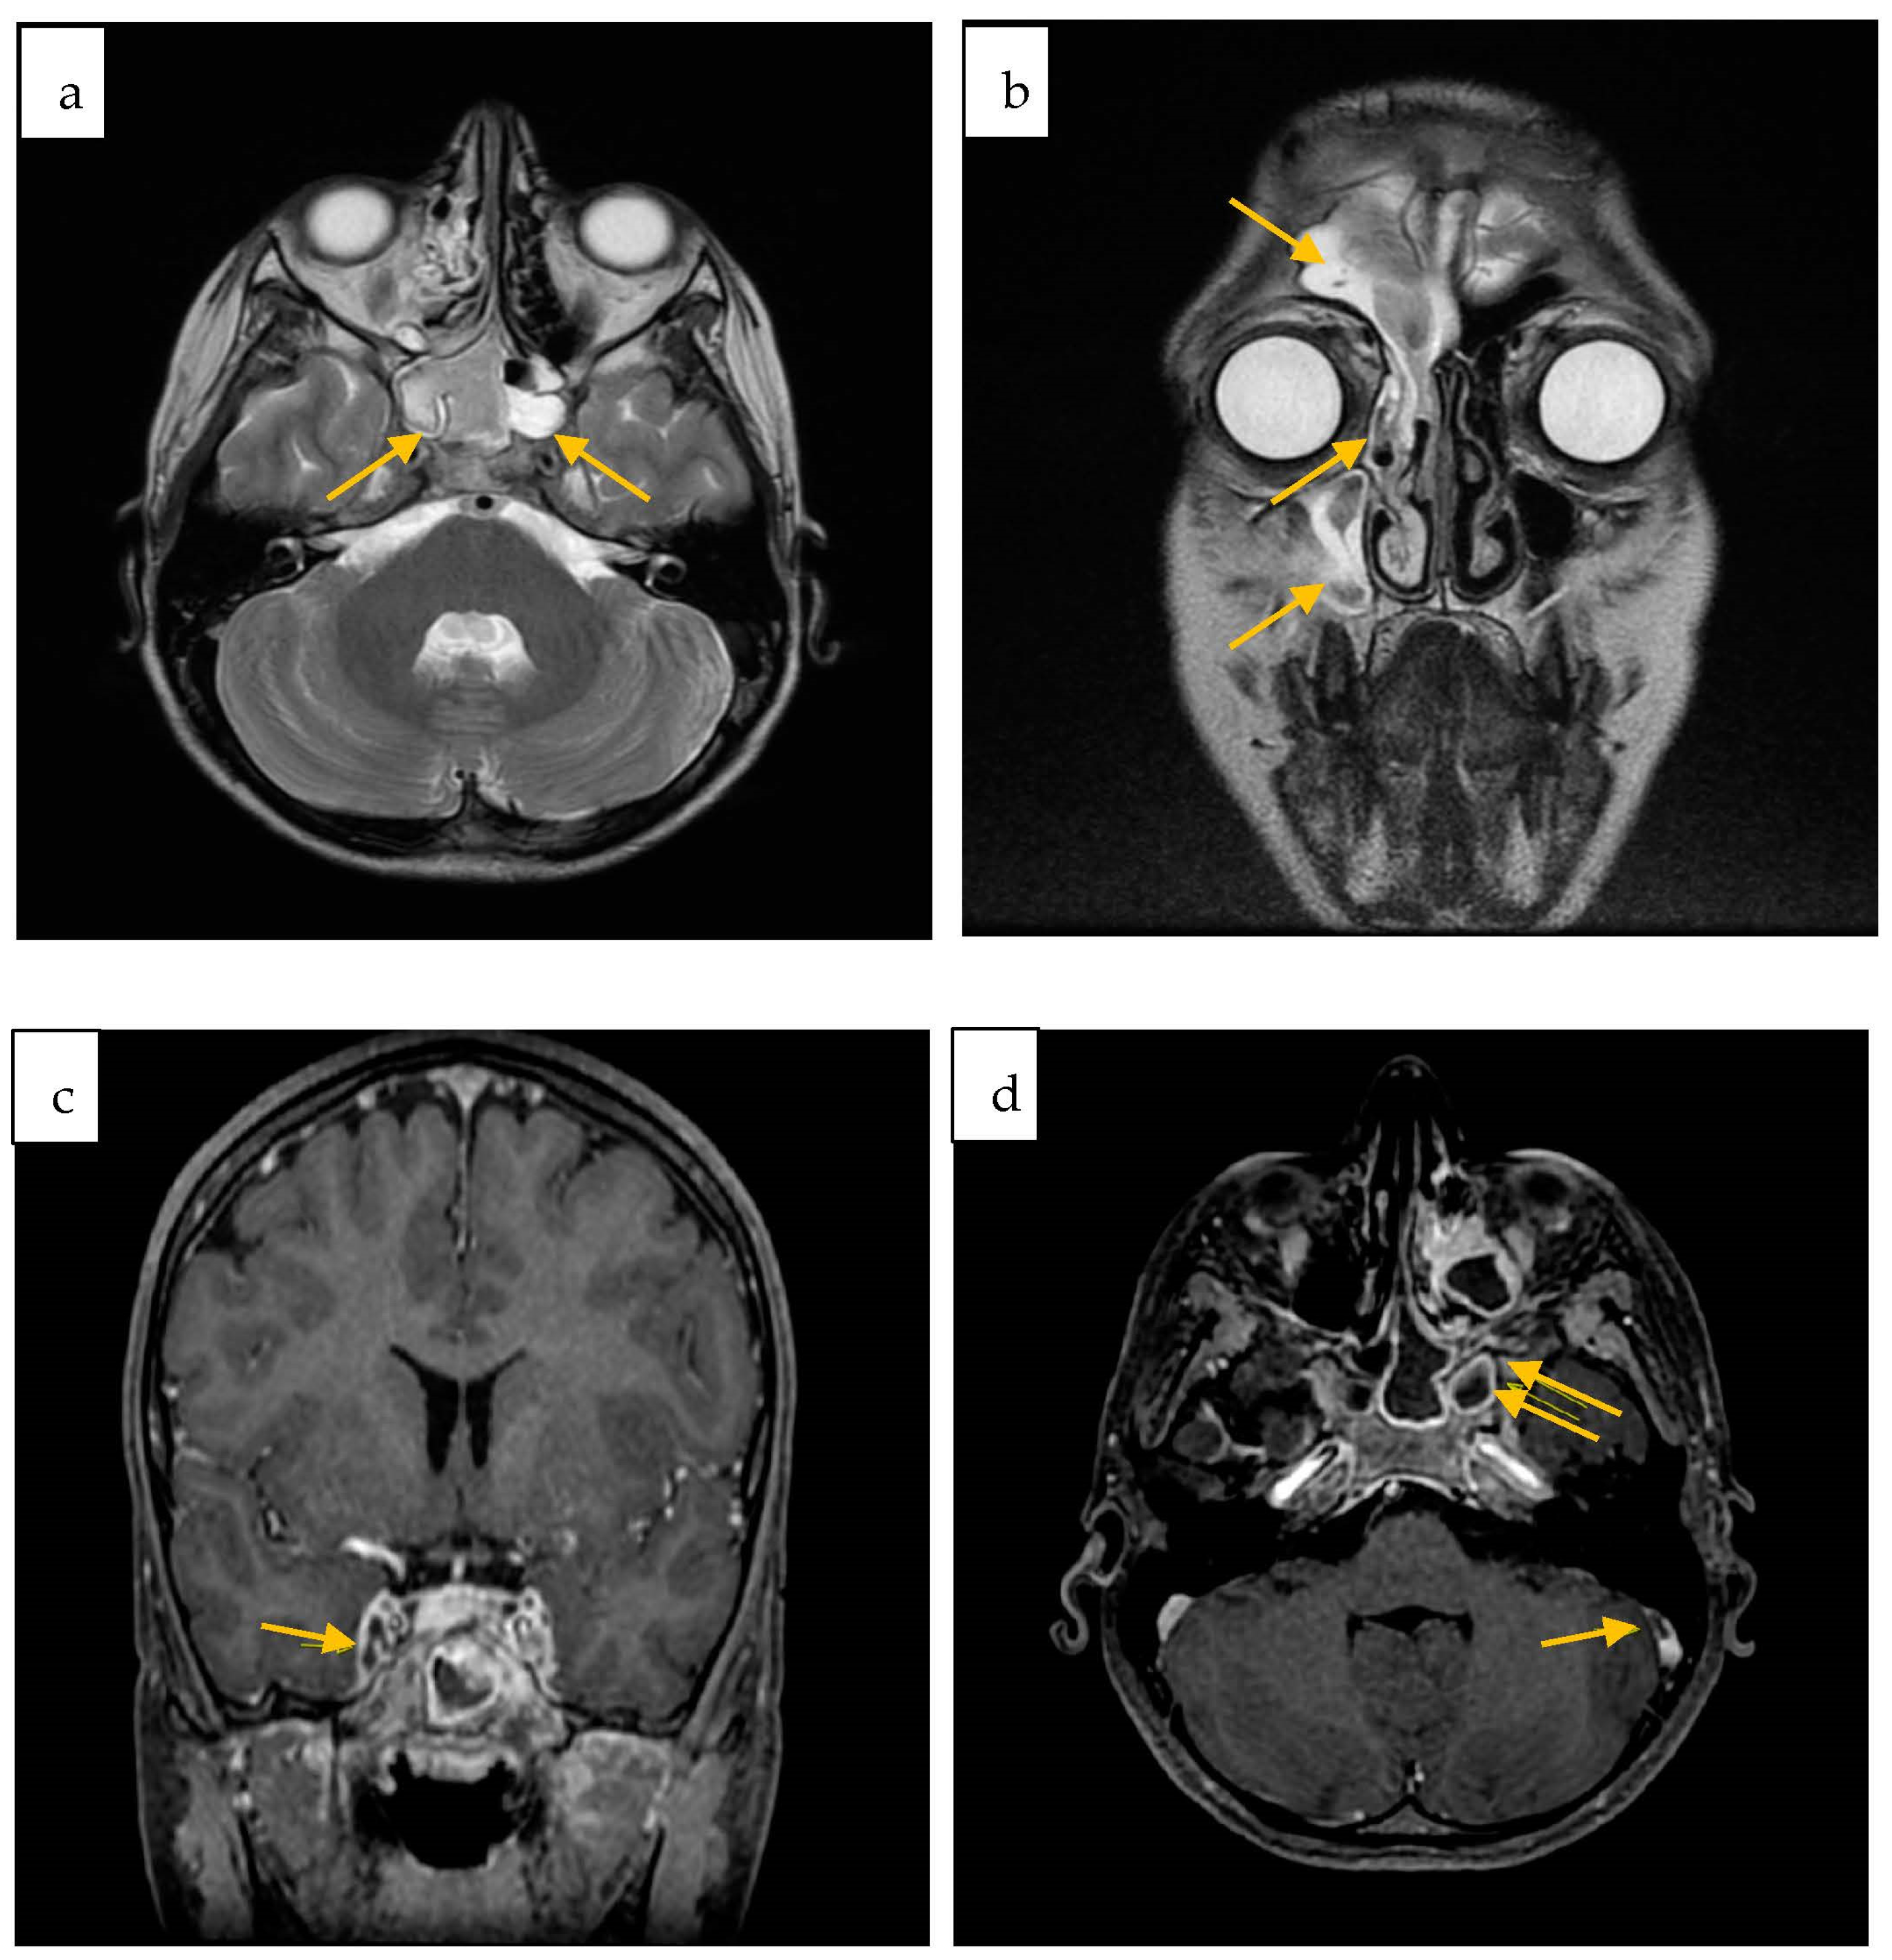

2. Case Report

| Colomba C. et al./Italy/2023 | 12 y | M | No | No | sinus drainage material | sinusitis, meningitis, CSVT | ceftriaxone + vancomycin + metronidazole → cefotaxime | healed |